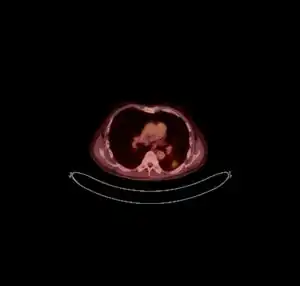

![]() ![]() text: From left to right: Cryptococcosis lung, cryptococcosis brain | |

CT scan lungs: mass in right upper lobe

FDG PET/CT - Multiple nodules (some cavitating) in the left lower lobe